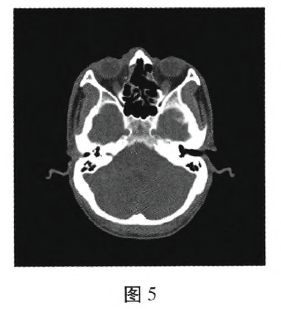

急诊计算机断层成像(computedtomography,CT)及三维重建:一片状致密影自右眼眼眶内下壁向左贯穿左眼眼眶内侧壁及左侧筛窦。眼球形态良好,眼环完整。外直肌、上直肌、视神经未见异常(图1、2、3)。

手术过程:全身麻醉。经鼻根部右侧皮肤切开,分离骨膜,注意保护泪囊,咬骨钳去除部分眼眶内下壁、右侧部分鼻根部鼻骨及部分鼻黏膜,暴露筛窦,沿异物纵轴退出异物。见异物大小约40mmx8mm(图4)。3.5%双氧水、碘伏原液以及生理盐水冲洗手术区,观察无异物残留,鼻腔碘纺纱条填塞,分层缝合。并行外侧结膜下探察,外直肌无损伤,予清创缝合,术后给予抗生素抗炎、预防破伤风等治疗,并针对视网膜挫伤进行相应治疗。术后7d拆线。术后半月右眼视力:0.1,眼球形态良好,眼球运动正常,复查CT:眼眶至筛窦内未见高密度影(图5)。